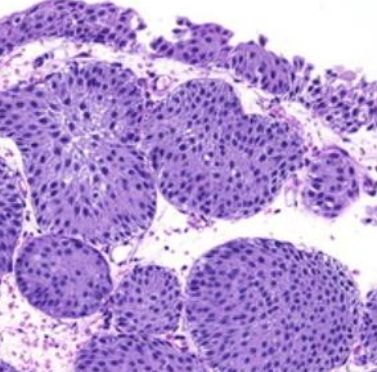

Oh my god, is that cancer?!

Nope, just an inverted urothelial papilloma.

Note how benign and bland the individual cells look. Typically 5-10 cells thick with a smooth stroma-epithelial interface and no stromal reaction.

There may also be some cystic lesions, like cystitis cystica associated with Von Brunn nests.